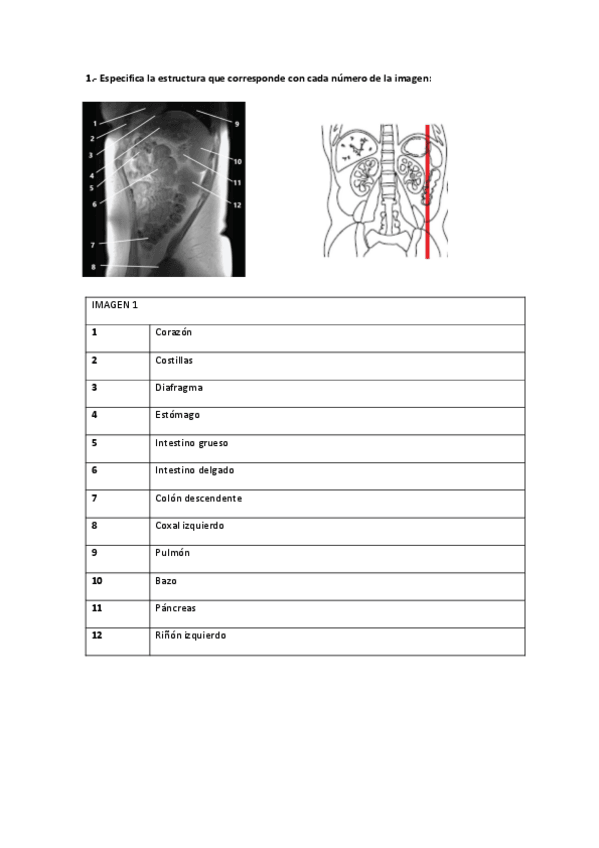

EVALUABLE-6-vertebras-RESUELTA66d67108d482c4c5a1977c4a315ef0aa.pdf